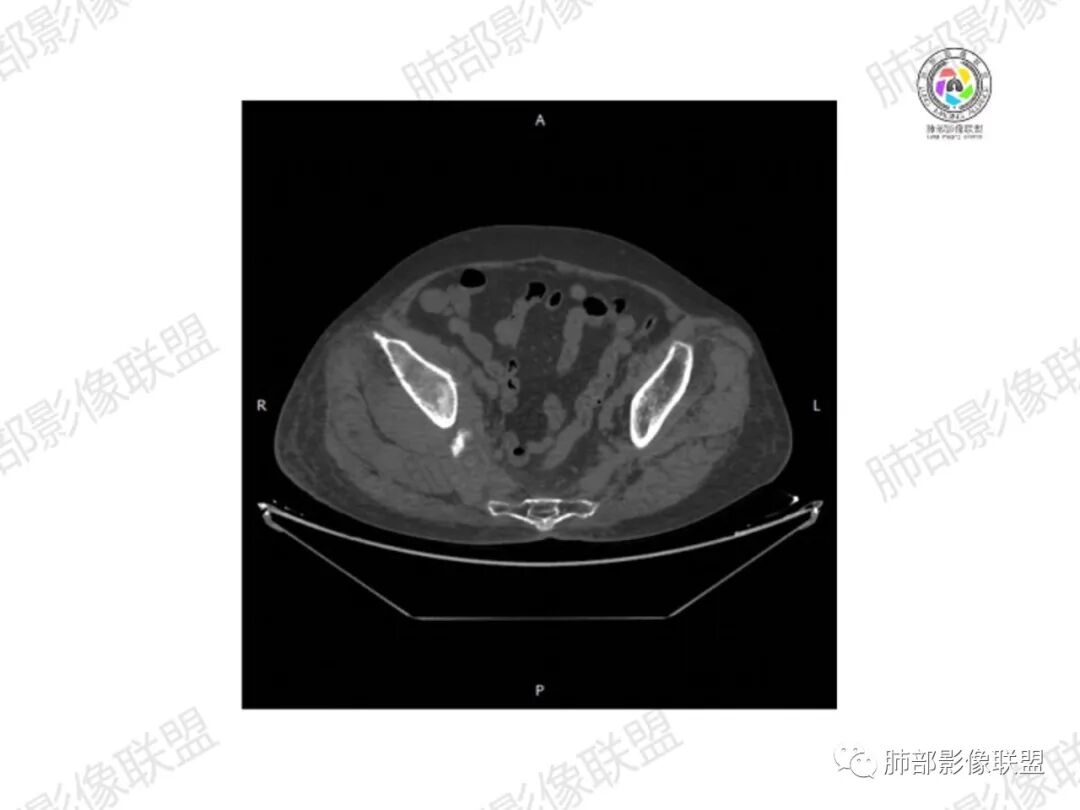

1.老年女性,直肠癌术后放疗后5年,右臀部疼痛4个月,加重半月

2.右髂骨轻度变形伴广泛骨质吸收破坏,边界不清且突破骨皮质。近中线区以溶骨性破坏为主,髂骨翼一侧则成骨性改变明显,骨表面见垂直骨针或花边样高密度瘤骨。

3.患骨多处皮质断裂,符合病理性骨折。注意折端可能会形成骨痂,但本例无论是形态还是部位都不符合骨痂。

4.患骨两旁(即盆骨内外)见边界不清的较大范围软组织快影,其间偶见骨化影。

5.双肺多发类圆形结节影,边界清楚,随机分布,其间多见钙化密度影。

6.双肺门及纵隔未见肿大淋巴结。

1.边界不清的骨质吸收破坏,溶骨明显,骨皮质突破,软组织肿块,种种迹象表明其恶性无疑!

2.但注意这是有“成骨”的恶性骨肿瘤!我们知道老年患者的骨原发性恶性肿瘤“成骨”非常少见。少数转移瘤可为成骨型或混合型,女性患者如乳腺癌骨转移等。在男性,最典型的成骨转移是前列腺癌。

本例右侧髂骨具有较为典型的“骨肉瘤”影像学特征,有边界不清的吸收破坏、有新生骨、形成软组织肿块等等。

3.双肺病灶符合转移瘤,伴有中央部分钙化者也以骨肉瘤转移较为多见。